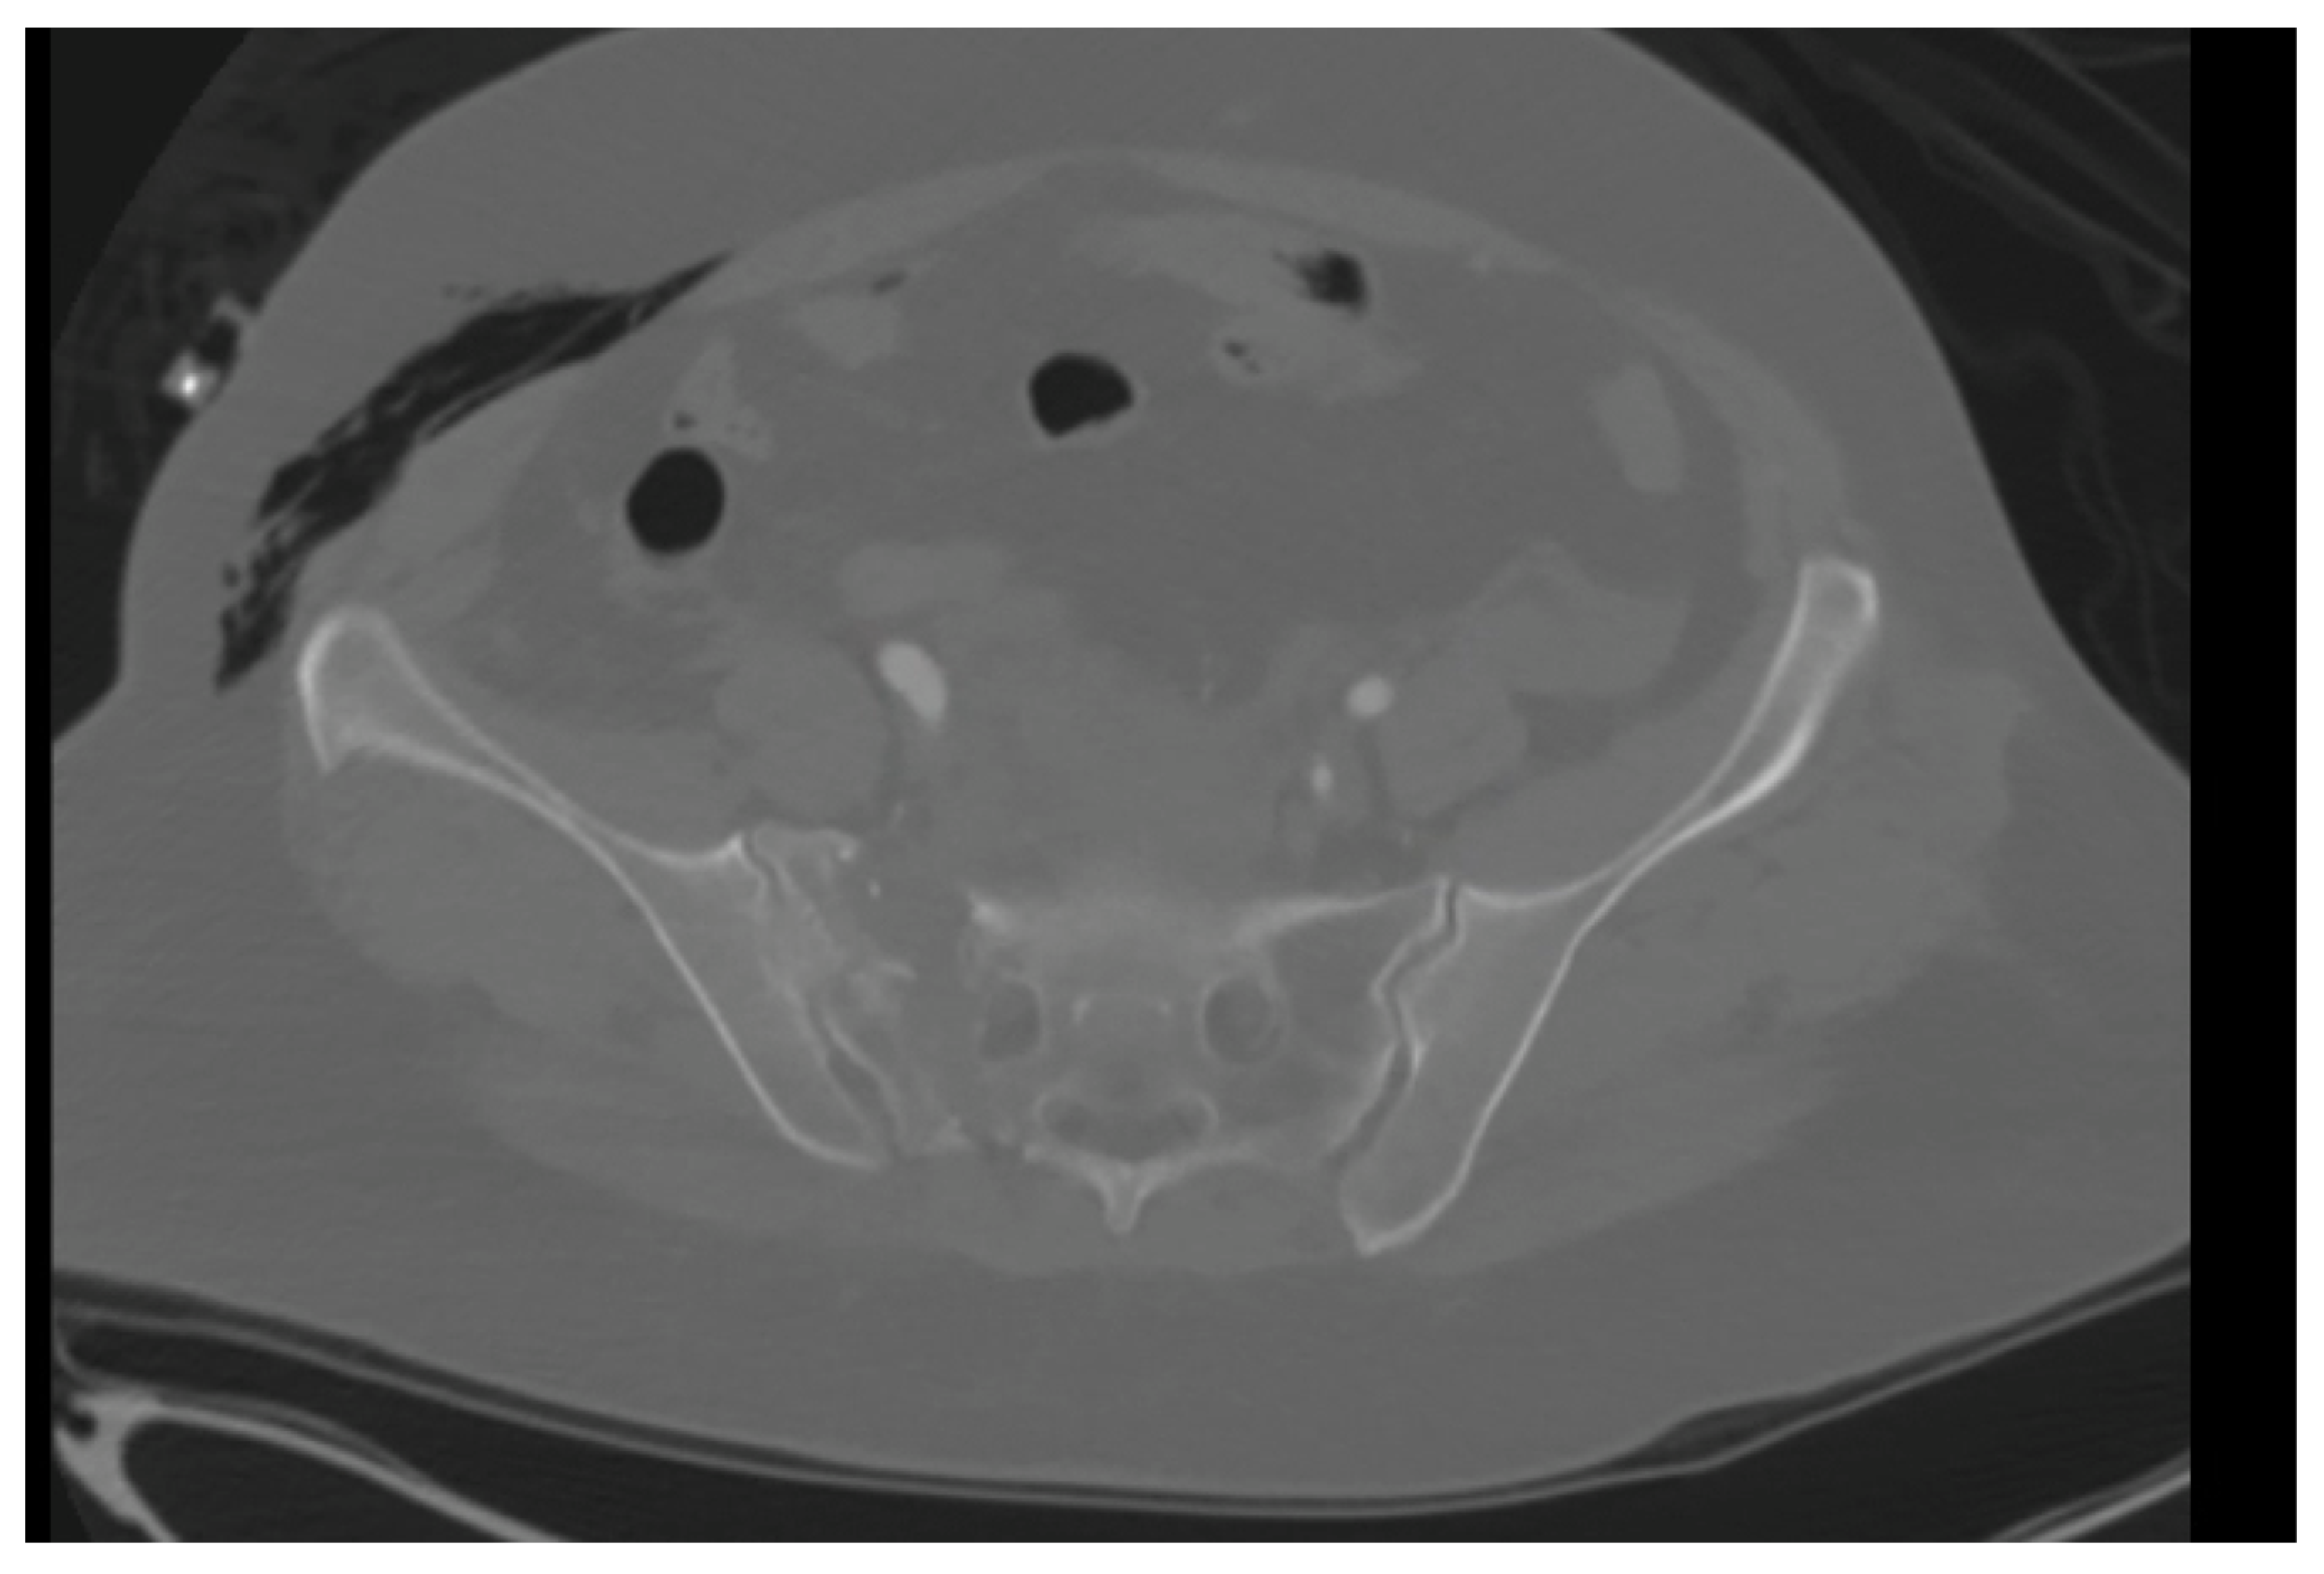

A 59-year-old female with no known past medical history presented to our level 1 trauma center, having been involved in a rollover motor vehicle collision. Plain radiographs and CT imaging demonstrated various orthopedic injuries including a Dennis type 1 vertical shear sacral fracture, bilateral superior and inferior pubic rami fractures (Figure 1 and Figure 2), right T5–T6, L1–L5, and left L2–L3 transverse process fractures, spinous process fractures of T7 and T9, and right posterior rib 4–7 fractures. Additional, non-orthopedic injuries included pneumothorax, retroperitoneal hematoma, grade 4 hepatic injury, grade 3 splenic injury, and grade 2 kidney injury. On day 3 of presentation, the patient was stable enough for operative fixation from the orthopedic surgery team.

Figure 2.

A still image from an axial CT of the pelvis in a skeletally mature individual better demonstrating a vertical shear sacral fracture.